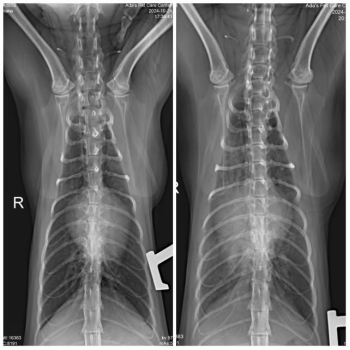

🔍 Diagnosis and Case AnalysisDuring a routine health check at our hospital, an abnormal cardiac silhouette was detected in the cat’s chest X-ray. Further echocardiography and abdominal ultrasound confirmed the diagnosis of pericardial diaphragmatic her…